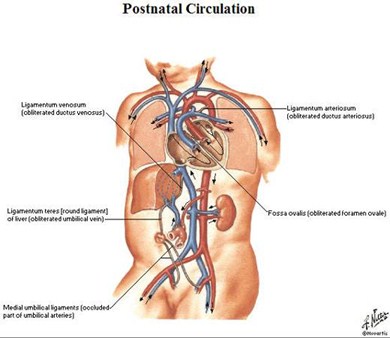

Placenta umbilical vein(ligamentum teres) hepatic sinusoid & ductusvenosus (ligamentumvenosum) portal vein IVC right atrium foramen ovale leftatrium left ventricle aorta systemiccirculation umbilicalarteries placenta

Fetal Circulation

From the umbilicus,umbilical vein passescephalad, slightly toright

Joins the left branch ofthe portal vein

The ductus venosusarises from the pointwhere the UV joins theleft portal vein

Ductus venosus entersIVC

UVC should be justabove diaphragm whereIVC enters RA (T8-T9)

Umbilical arteriesare directcontinuation ofinternal iliacarteries

UAC will usuallyenter aorta viainternal iliac artery

UAC should thenpass up aorta,above diaphragm,between T6 and T9

Whatever Became of…

Real Name

Stage Name

Umbilical vein

Ligamentum teres

Umbilical arteries

Medial umbilicalligaments

Ductus venosus

Ligamentum venosum

Ductus arteriosus

Ligamentumarteriosum